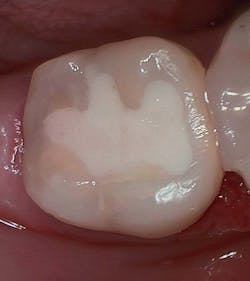

Figure 3 shows the final restoration immediately after placement. Figure 4 shows the final restoration of an initial caries lesion on the buccal. The clinician anticipated maturation of the glass-hybrid in choosing a lighter shade of A2, which initially appeared much too light. A slightly darker shade may have been more appropriate.